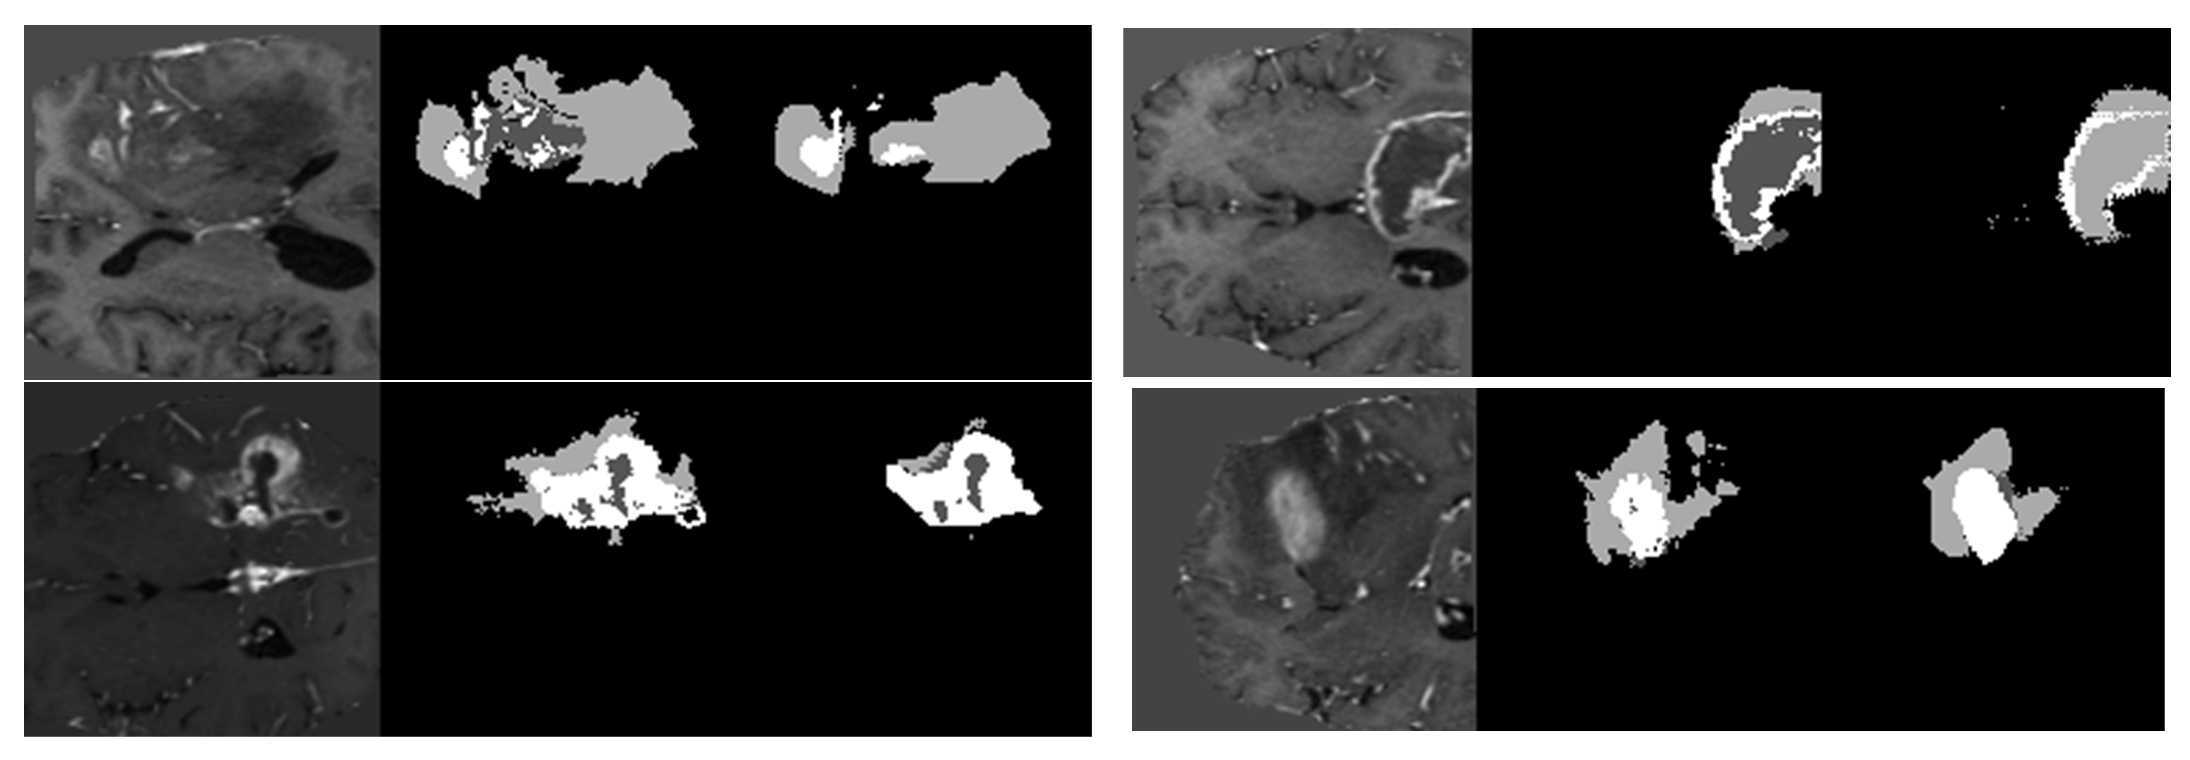

The model has been trained for 100 epochs, and the quality of the segmented images for some epochs is shown in Figure 8. The first part of image is the input image fed to the model. The second part is the maximum segmented region and last part is the final segmented output from the RTGAN model.

Figure 8.

Segmented Output.